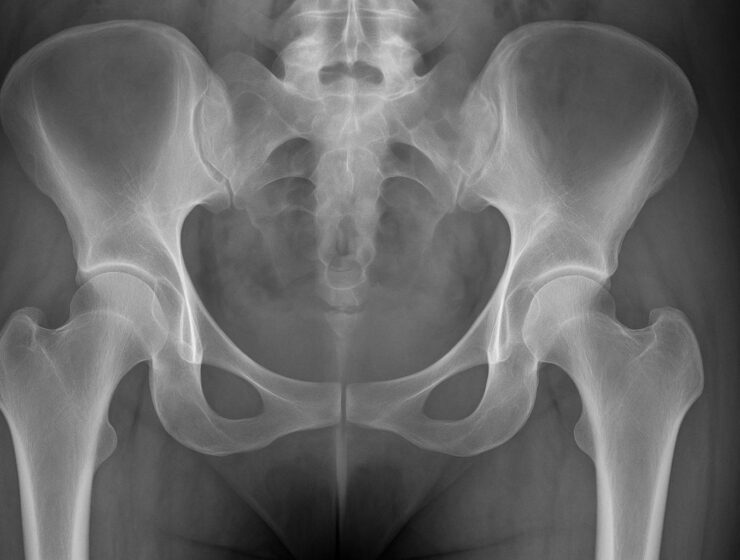

Entrevista: María Pérez, creadora de La Pelvis Revolution. El suelo pélvico. Ese Universo olvidado y adormilado que sostiene mucho más que nuestra anatomía.…